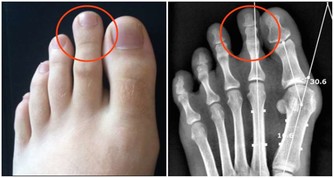

1.一到春季或秋季,頻繁的打噴嚏流鼻涕

2.黑眼圈大而重

3.夜裡睡覺時張口呼吸打呼嚕

4.習慣性揉鼻子、揉眼睛、擠眉弄眼

5.容易出現皮膚瘙癢

不停流鼻涕、鼻塞、打噴嚏的症狀和流行性感冒十分相似,很多時候家長會將鼻炎誤會成感冒,而耽誤了治療。

過敏性鼻炎是因為接觸了過敏物質,發作有著明顯的季節性,噴嚏持續時間長且劇烈,鼻涕一般呈稀薄水狀,慢性反復發作。所以,家長一定要做好區分及時就醫。